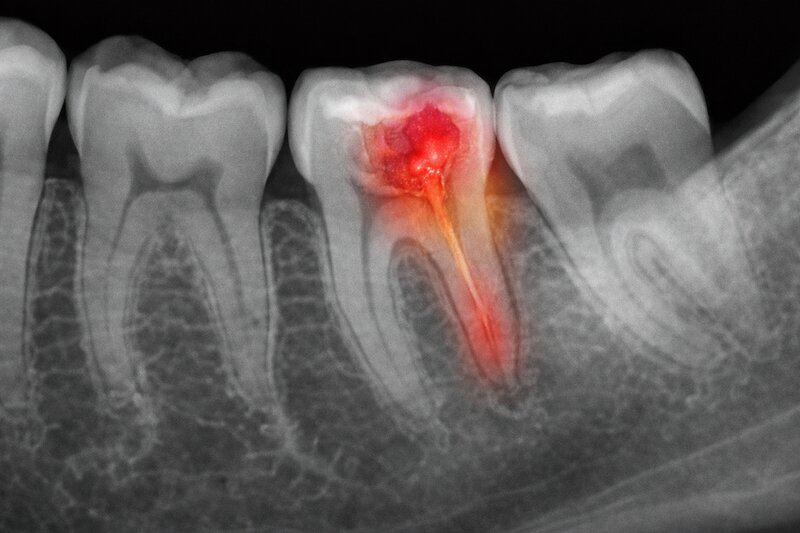

Khi sâu răng tiến triển sâu vào bên trong, vi khuẩn không chỉ phá huỷ mô cứng của răng mà còn có thể xâm nhập vào buồng tuỷ và gây viêm tuỷ răng. Ở giai đoạn này, tình trạng không còn chỉ là tổn thương bề mặt mà đã liên quan đến mô bên trong răng và nguy cơ nhiễm trùng.

Nếu viêm tuỷ kéo dài hoặc không được xử lý, mô tuỷ có thể bị tổn thương nặng hoặc hoại tử. Nhiễm trùng từ trong răng cũng có thể lan ra vùng quanh chóp chân răng, tạo thành ổ viêm kèm dịch viêm, mô hoại tử và vi khuẩn tích tụ. Đây là những yếu tố có thể góp phần tạo ra mùi hôi trong khoang miệng, đặc biệt khi tình trạng viêm nhiễm tồn tại dai dẳng.